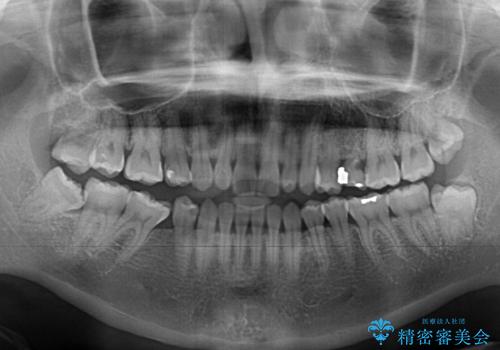

- 隙間の多い歯列や傾斜した奥歯、むし歯の酷い残存乳歯を気にして来院された患者様です。

歯列はワイヤー矯正にて改善することとしましたが、上下歯列にも隙間があったので、舌の突出癖を改善するトレーニングを徹底的に行うこととしました。

傾斜した下顎の奥歯は、矯正治療にてまずは歯軸を改善させ、隙間が閉じられるようであればそのままに、閉じられないようであればインプラント治療を行うこととしました。

上顎のむし歯の酷い残存乳歯は抜歯をし、矯正治療の途中でインプラントを埋入、矯正治療後に補綴治療を行うこととしました。